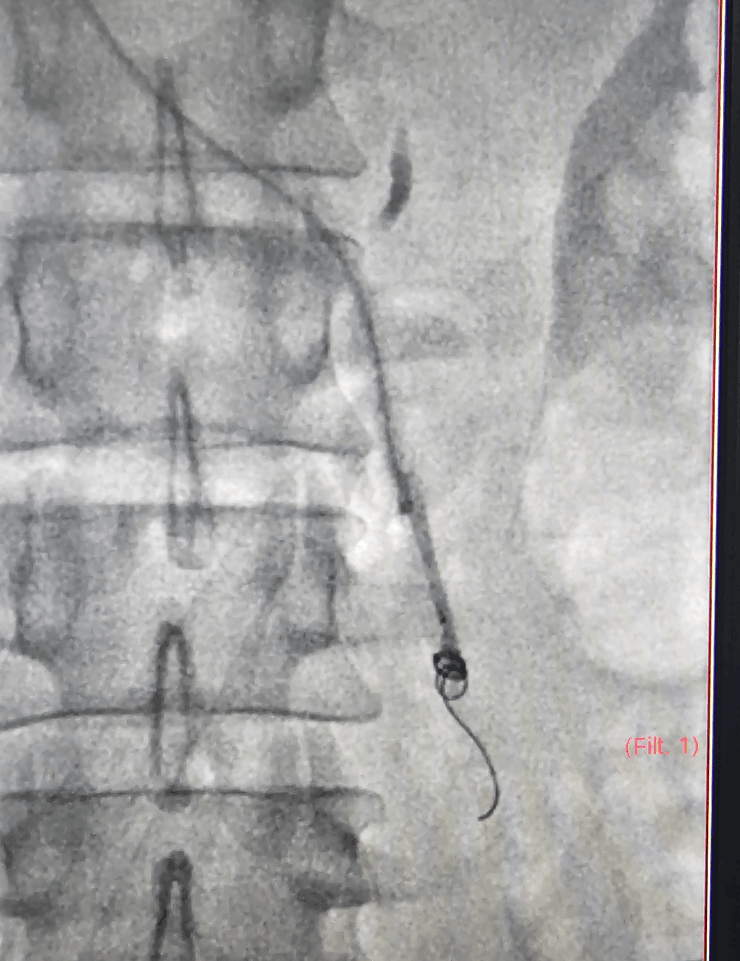

The procedure is done under fluoroscopy (X‑ray) guidance, usually with local anesthesia and light sedation.

- Vein access through a small puncture in the groin or neck vein.

- Venogram to map abnormal testicular veins and confirm varicocele.

- Coil embolization and/or other embolic agents are used to block the refluxing veins.